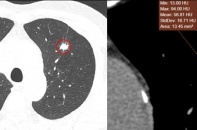

Hơn 20 năm hút thuốc lá, người đàn ông 62 tuổi nhận về kết quả ung thư phổi giai đoạn 4 đã di căn trong sự ngỡ ngàng, bởi bệnh diễn tiến âm thầm, lặng lẽ, các triệu chứng chỉ mới chớm xuất hiện.